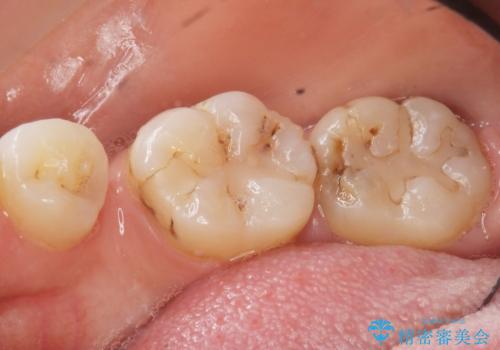

- 奥歯の隙間を治したいとご希望された患者様です。

学生時代に舌側矯正されていたものの、通院が大変になり治療を途中でやめてしまい、奥歯の間に隙間が残ってしまったそうです。

矯正せずに早く治したいという強いご希望とう蝕があることから、セラミッククラウンによる補綴治療で隙間を閉じることにしました。

矯正せずに隙間を閉じることができ、ご満足頂けました。

セラミッククラウンの審美的な仕上がりと咬み心地に喜んで下さいました。